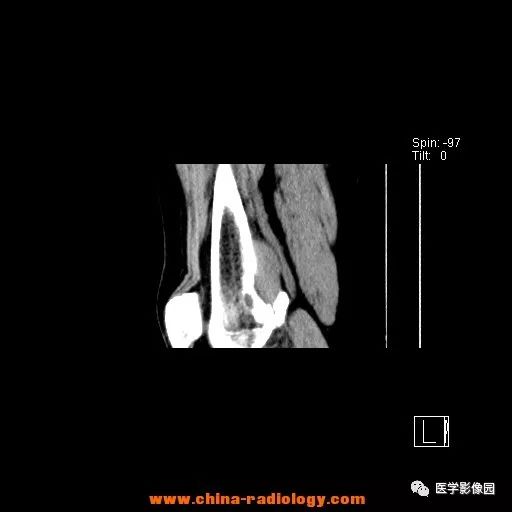

患者女性,29岁,右膝关节痛疼3月余,局部无红肿。

影像学表现:右股骨远端外后方可见局限性骨质破坏及软组织肿块,边界清楚。

病理结果:梭形细胞瘤